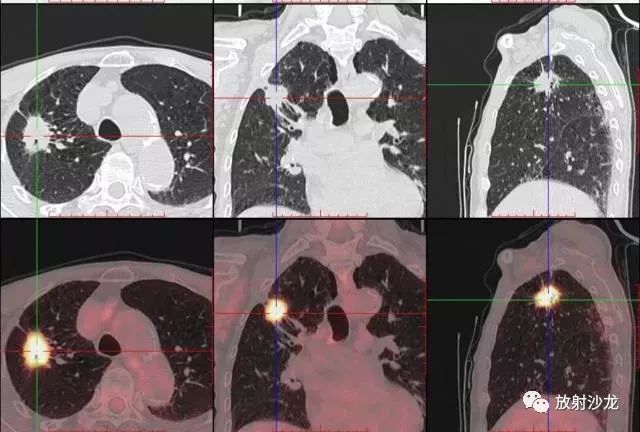

PET-CT等于PET+CT,包含PET(功能分子影像)與CT(解剖影像)的最優(yōu)化組合;即同時具有PET和CT的功能,但它絕不是二者功能的簡單疊加,因為PET與CT優(yōu)勢互補,“1+1>2”。PET-CT除了具備PET和CT各自的功能外,其獨有的融合圖像,將PET圖像與CT圖像融合, 可以同時反映病灶的代謝,可以早期診斷疾病的同時,明顯提高診斷的準(zhǔn)確性。

18F-FDG(氟脫氧葡萄糖)是葡萄糖的類似物,是臨床最常用的顯像劑;18F-FDG能反映體內(nèi)葡萄糖利用狀況。腫瘤細胞內(nèi)可積聚大量18F-FDG,但是18F-FDG僅僅是葡萄糖類似物,腫瘤細胞攝取后不能進一步代謝,屬于“只進不拉”,能在腫瘤細胞內(nèi)積聚,經(jīng)PET-CT顯像可顯示腫瘤的部位、形態(tài)、大小、數(shù)量及腫瘤內(nèi)的放射性分布。同時腫瘤細胞的原發(fā)灶和轉(zhuǎn)移灶具有相似的代謝特性,一次注射18F-FDG就能方便地進行全身顯像,18F-FDG PET-CT全身顯像對于了解腫瘤的全身累及范圍具有獨特價值。